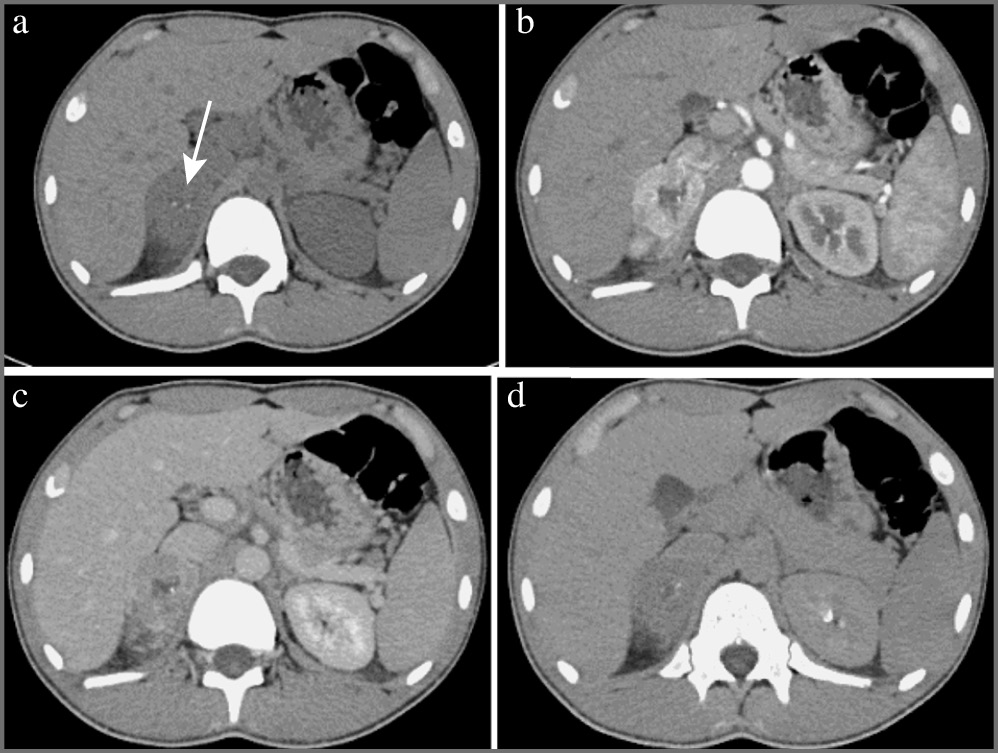

Аденома – доброкачественное образование надпочечника, она составляет около 80% всех образований надпочечников. На КТ-изображениях аденомы обычно представляют собой образования с четкими ровными контурами овальной формы, однородной структуры, размером, как правило, менее 3 см. При динамическом наблюдении размер аденом не меняется или медленно увеличивается в пределах нескольких миллиметров в год (рис. 1) [2].

Рис. 1. Аденома надпочечника с низким содержанием жира (стрелка). МСКТ, аксиальная проекция: а – нативная фаза; b – артериальная фаза; c – венозная фаза; d – отсроченная фаза. Примечание. МСКТ – мультиспиральная компьютерная томография.

В зависимости от количества внутриклеточных жировых включений различают аденомы с высоким (80%) и низким (20%) содержанием жира, что проявляется характерной КТ-картиной. Так, аденомы с высоким содержанием жира представлены на нативных изображениях образованиями плотностью до 10 ед. Н.

Все аденомы имеют патогномоничное накопление контрастного препарата с быстрым «вымыванием» его после внутривенного болюсного контрастирования, что позволяет дифференцировать аденомы с другими заболеваниями надпочечника, например злокачественными новообразованиями и феохромоцитомами.

Для оценки характера контрастирования в большинстве случаев проводится четырехфазное КТ-сканирование с болюсным введением неионного йодсодержащего контрастного препарата со скоростью введения 2–4 мл/с, дозой контрастного вещества с концентрацией 300–350 мг йода/мл (60–76%) не менее 1 мл/кг массы тела пациента (лучше – 100–140 мл). Исследование проводят в нативную, артериальную (18–25 с после начала введения болюса контрастного препарата или 10 с после достижения пика 100–150 ед. Н на болюс-трекере), венозную (55–65 с от начала введения болюса) и отсроченную (15 мин после введения контрастного препарата) фазы. Для аденом максимальное накопление контрастного препарата в большинстве наблюдений определяется в венозную фазу.